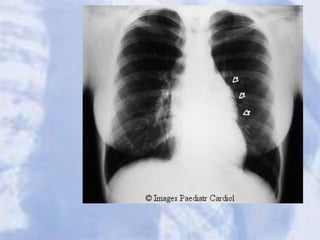

Pulmonary artery stenosis with cardiomegally likely

secondary to stenosis.